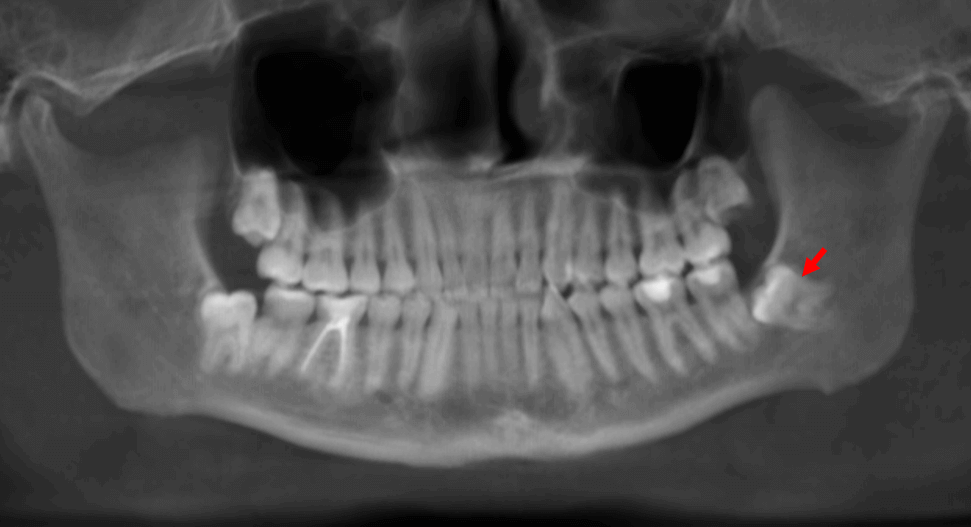

Fig.1

En la evaluación con tomografía volumétrica cone beam, se observa, en la reconstrucción panorámica de ambos maxilares (Fig.1), la impactación de los terceros molares superiores, impactado den posición vertical contra los órganos dentarios 17 y 27, respectivamente; la impactación del órgano dentario 38 en posición mesioangular (flecha roja) en el cual se observa una aparente dilaceración radicular y la impactación del órgano dentario 48 contra el borde anterior de la rama ascendente mandibular.